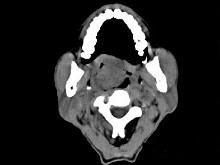

问题 男性,57岁,睡觉打鼾,近来加重,CT扫描如图所示,请选择正确的描述和答案 ( )

选项 A、考虑为鼻咽癌 B、考虑为鼻咽部多形性腺瘤 C、肿块内密度尚均匀,其上方见较多钙化影 D、肿块边缘大部清楚,邻近结构未见明显受侵 E、鼻咽腔偏右侧可见类圆形软组织块影

答案 BCDE